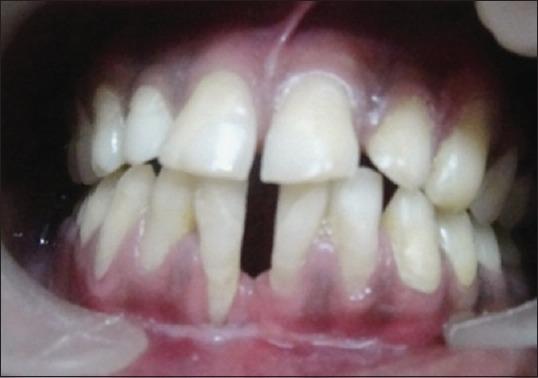

Miller's class III gingival recession is a common entity observed in individuals, posing a difficult situation for the clinicians to treat. Large fenestration defects with cervical abrasion compromise the esthetics resulting in poor prognosis. Obtaining predictable and esthetic root coverage has become an integral part of periodontal therapy. The present case report describes a situation where class III gingival recession with cervical abrasion was seen in the lower central incisors. The patient was successfully treated with a combination of restorations (Filtek Z350(®) composite resin) to fill the defect, followed by fenestration procedure to increase the vestibular depth and subsequently with grafting procedure (soft tissue autograft with bovine-derived xenograft collagen [Bio-oss]). Though the results were not tangible esthetically, it was functionally successful as evidenced during the follow-up period.

米勒Ⅲ类牙龈退缩在个体中很常见,给临床医生的治疗带来难题。伴有颈部磨损的大穿孔缺损会影响美观,导致预后不良。获得可预测且美观的牙根覆盖已成为牙周治疗不可或缺的一部分。本病例报告描述了在下颌中切牙出现Ⅲ类牙龈退缩伴颈部磨损的情况。患者通过联合修复(Filtek Z350®复合树脂)填充缺损、开窗手术增加前庭深度,随后进行植骨手术(自体软组织移植联合牛源异种移植胶原蛋白[Bio-oss])成功得到治疗。尽管在美观方面效果不明显,但在随访期间证明功能上是成功的。